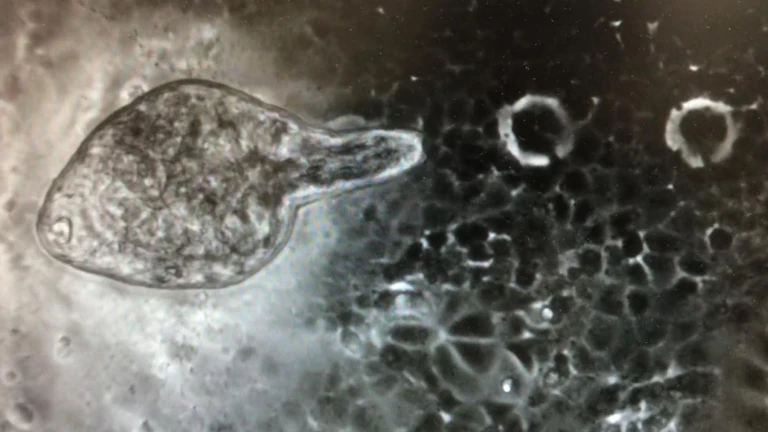

Entrevistamos a Mar Siles, directora del IRNASA, sobre los efectos antivirales que posee el gusano Fasciola Hepática.